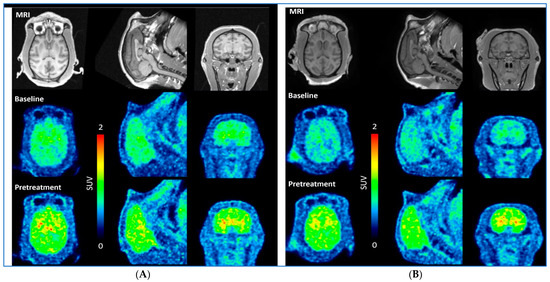

| Radioligand | Weight (kg) | Injected Radioactivity (MBq) | Molar Activity (GBq/µmol) | Injected Mass (µg) | Condition | Dose mg/kg |

|---|---|---|---|---|---|---|

| [11C]BIO-2008846-A | 7.1 | 157 | 558 | 0.1 | Baseline | - |

| 160 | 452 | 0.13 | Pretreat | 1 | ||

| [11C]BIO-2008846-A | 8.4 | 160 | 359 | 0.17 | Baseline | - |

| 118 | 518 | 0.08 | Pretreat | 1 |